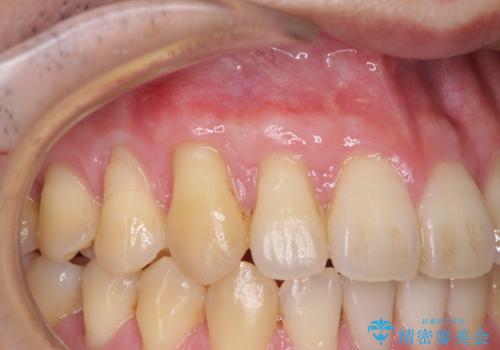

八重歯の歯根が見えている点も気になっているので、矯正歯科治療後に歯肉移植による根面被覆を行うこととしました。

矯正治療により元々気になっていた八重歯と、反対咬合が改善された歯の2本に対して根面被覆を行い、審美面の改善も達成しました。